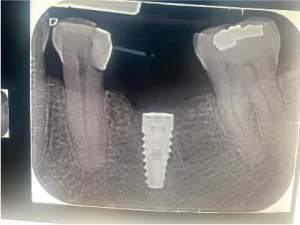

Se decide colocar implantes de zirconio, rehabilitación dental final con coronas de zirconio.

se realiza planeación quirúrgica computarizada, confección de guía de fresado y de provisionales acrílicos.